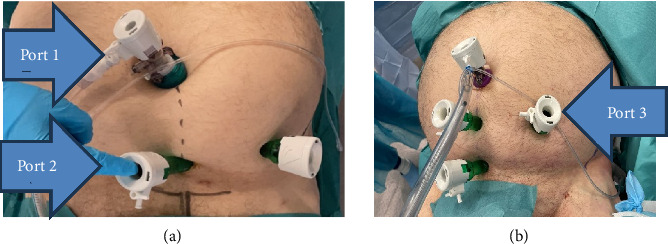

背景和目的:在传统开放手术中对髋臼骨折进行操作时,关键结构的可视化可能具有挑战性。近年来,已有多篇关于腹腔镜辅助髋臼手术的病例报道。因此,我们利用腹膜外内窥镜进一步发展了这种方法来处理髋臼骨折。手术方法手术技术:由经验丰富、熟悉腹膜外腹腔镜技术的疝气外科医生协助进入髋臼区域,以便骨科医生通过腹腔镜端口用钢板和螺钉集中固定该区域。结果:我们在尸体实验室中开发了这种手术技术,在腹膜外内窥镜的可视化下,我们可以轻松地对七具尸体的左右两侧髋臼区域进行固定和钢板安装。结论:髋臼骨折的全内窥镜微创手术与传统的开放手术相比,具有康复快、失血少、伤口并发症少等显著优势。根据我们在尸体上获得的初步经验,与开放手术相比,这种微创方法具有更好的可视性,更容易进入骨盆区域原本狭窄且难以进入的骨折部位。此外,这种微创方法在内窥镜和荧光透视的联合可视控制下精确放置钢板似乎是可行的。这种新方法在现实生活中微创治疗髋臼骨折的实用性,特别是考虑到适当的骨折复位的实用性,应在未来的临床试验中得到证实。

Background and Objectives: When operating on acetabular fractures in conventional open surgery, visualization of crucial structures can be challenging. In recent years there have been several case reports on laparoscopy-assisted acetabulum surgery in the literature. Therefore, we have developed this method further using extraperitoneal endoscopy to manage acetabulum fractures. Methods: Operative technique: An experienced hernia surgeon familiar with the totally extraperitoneal laparoscopic technique facilitates access to the acetabulum area so that orthopaedic surgeons can focus on fixing the area with a plate and screws through laparoscopy ports. Results: We developed this operative technique in a cadaver laboratory where we could easily fix and plate the acetabulum area with extraperitoneal endoscopy visualization in seven cadavers both on the left and right sides. Conclusions: A minimally invasive full endoscopic procedure for acetabular fractures offers significant benefits over traditional open surgery due to faster rehabilitation, potentially less blood loss, and fewer wound complications. According to our initial experiences with cadavers, this minimally invasive method appears promising in terms of superior visibility and easier access to the otherwise narrow and difficult fracture site in the pelvic region compared to open surgery. Furthermore, this minimally invasive method seems feasible for exact plate placement under combined endoscopic and fluoroscopic visual control. The usefulness of this novel method in the minimally invasive treatment of acetabular fractures in real life, especially considering the practicality of proper fracture reduction, should be confirmed in future clinical trials.